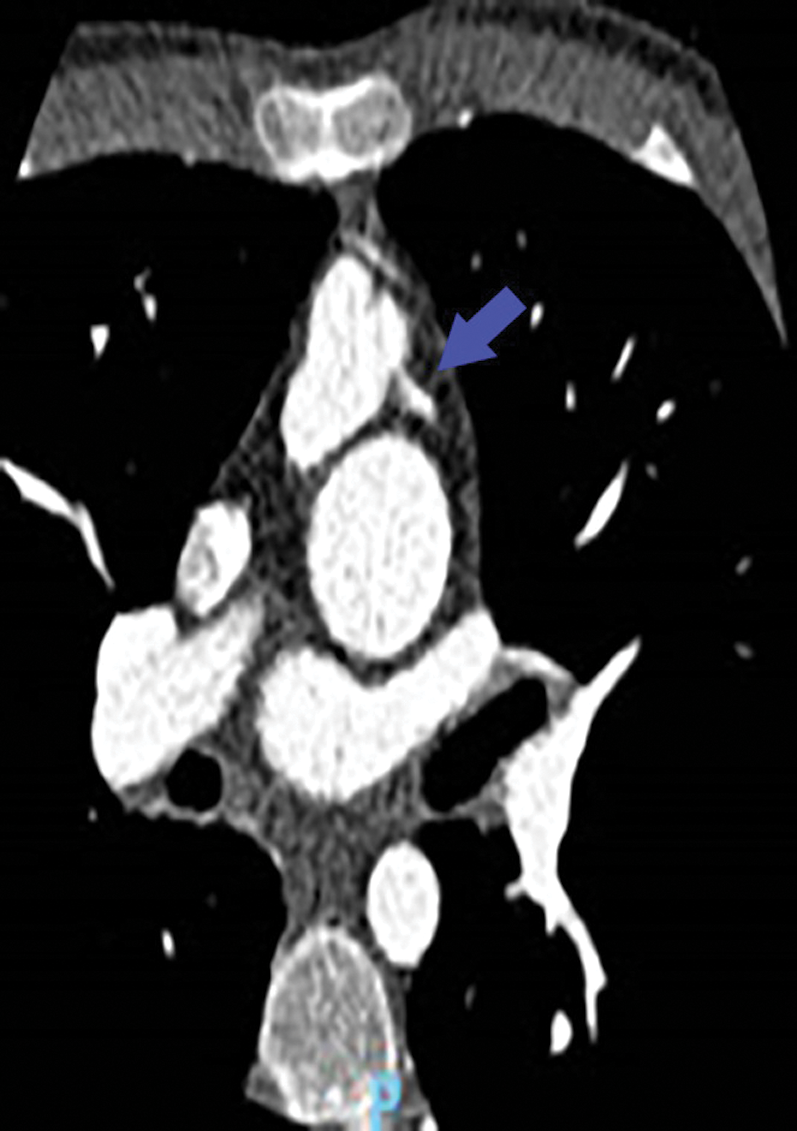

The patient was asymptomatic. The physical examination at admission showed a systolic murmur 3/6 maximum at the pulmonary focus and radiating into the back and no signs of heart failure was present. The electrocardiogram was normal, and the echocardiographic study showed a mild septal dyskinesia. The cardiac catheterization and the angio-CT demonstrated a rare coronary pattern: 1- proximal LAD and 2-RCA-Cx-distal LAD pattern (posterior loop) and severe proximal stenosis of “LAD” arising from pulmonary artery (Figs. 1–4).

Figure 2: Angio-CT: LAD coronary arising from pulmonary artery